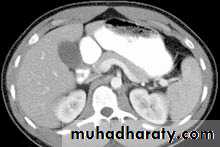

hepatic mets

hepatic mets,arterial phase

hepatic mets venous phase